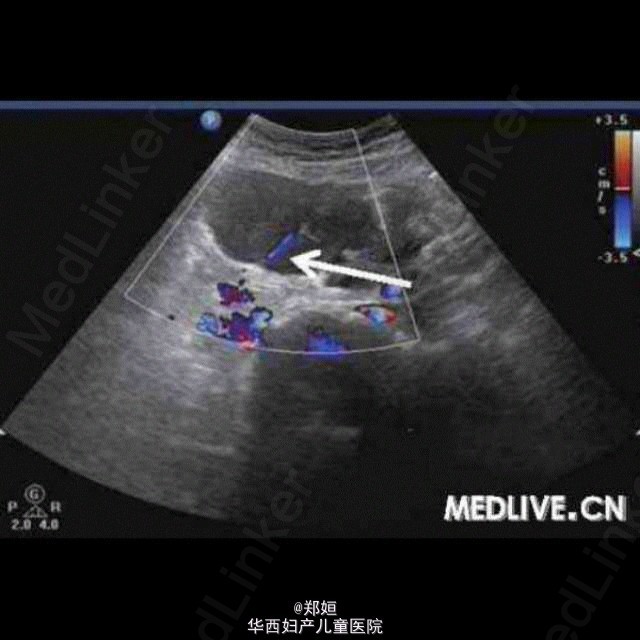

病历资料:女,34岁,6年前体检发现左附件区有一直径为2 cm的肿物,因肿物体积较小而未治疗。5年前患者无明显诱因地出现月经期腹痛 ,伴腰酸腹胀逐渐加重,须服止痛药缓解,B超复查显示,盆腔肿物体积增大。超声检查:子宫肌层回声欠均匀,子宫后壁肌间隐约可见3.8 cm×3.5 cm×3.7 cm中等回声包块,边界欠清,点状血流信号(图1)。右附件可见6.7 cm×5.8 cm×5.3 cm囊性包块,边界清,外形规则, 内为液性暗区伴细密光点,囊壁可见点状血流信号(图2和图3);子宫左上方可见6.1 cm×4.5 cm×4.6 cm囊性包块,边界清,外形尚规则 ,内为液性暗区伴细密光点,内可见分隔,隔壁可见条状血流信号(图4)。 诊断:子宫增大;子宫腺肌症;双附件区囊性包块。 术中所见:子宫前位,宫体球形,质硬;子宫后壁外突瘤核,界限不清。双侧卵巢均囊性增大,囊肿内为巧克力样物质,均为多房,与阔韧 带后叶、乙状结肠和子宫后壁粘连。 http://case.medlive.cn/obgyn/case-article/show-46213_207.html